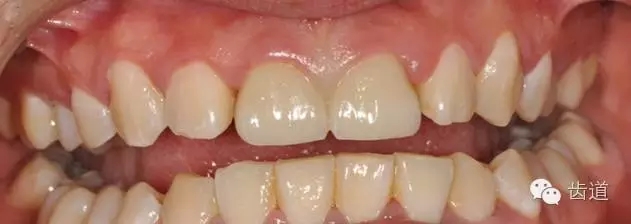

初診時(shí)口內(nèi)照

檢查:11、21烤瓷聯(lián)冠修復(fù)體,唇側(cè)部分崩瓷,可見(jiàn)金屬基底冠,邊緣不密合,牙齦紅腫,咬合緊,無(wú)明顯松動(dòng),X片示:11、21根管透射,根尖區(qū)陰影。

診斷:11、21烤瓷冠崩瓷。